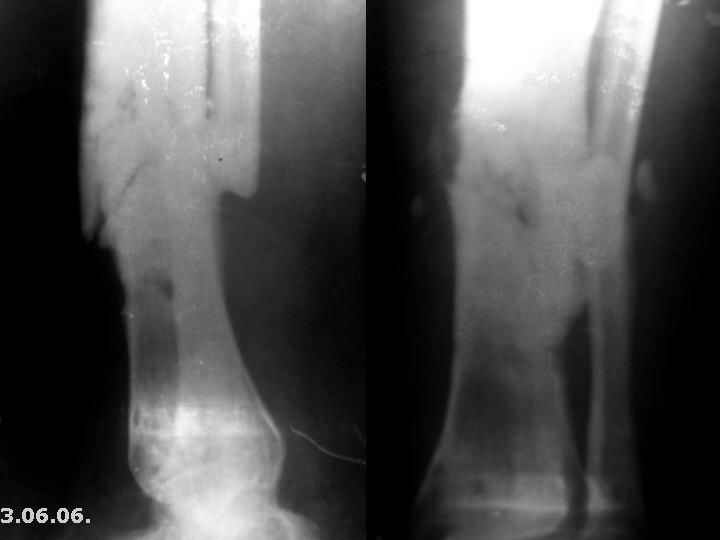

Мужчина, 29 лет. Состоит на лечении в ЦРБ.Диагноз: Замедленно сростающийся со смещением повторный перелом обеих костей левой голени вс/3-н/3, состояние после ВЧКО, хронический остеомиелит костей левой голени, свищевая форма,трофический синдром, смешанная контрактура левого коленного, голеностопного суставов.

Травма 20.12.04. - открытый 2Б тип, оскольчатый перелом обеих костей левой голени в с/3-н/3 сосмещением отломков (ДТП). 20.12.04.- ВЧКО костей голени АВФ спице-стержневого типа, ПХО ран.Лечился амбулаторно. Перелом длительно не сростался. АВФ демонтирован 22.06.05., разрешена нагрузка на ногу, после чего появилась подвижность в области перелома. 8.07.05. - ВЧКО, туннелизация по Беку. Течение осложнилось развитием спицевого остеомиелита, 1.11.05. АВФ демонтирован, получал консервативное лечение. После нормализации состояния 17.11.05.- секвестрэктомия, ВЧКО голени.12.04.06. АВФ демонтирован.

3.06.06.повторная травма - закрытый повторный перелом левой б/б кости в с/-н/3, лечился методомгипсовой иммобилизации.

Место болезни - ось голени искривлена. Kеллоидные рубцы в местах проведения спиц, по передней поверхности голени. По передней и внутренне-боковой поверхности голени в определяется 3 свища с умеренным серозным отделяемым. Отек голени и сустава, движения в коленном и голеностопном суставах ограничены, неврологических расстройств в стопе нет.

Снимки, конечно, оставляют желать. Ладно, пробуем предложить решение в условиях недостатка информации. В том числе не зная о доступных на месте методах лечения.